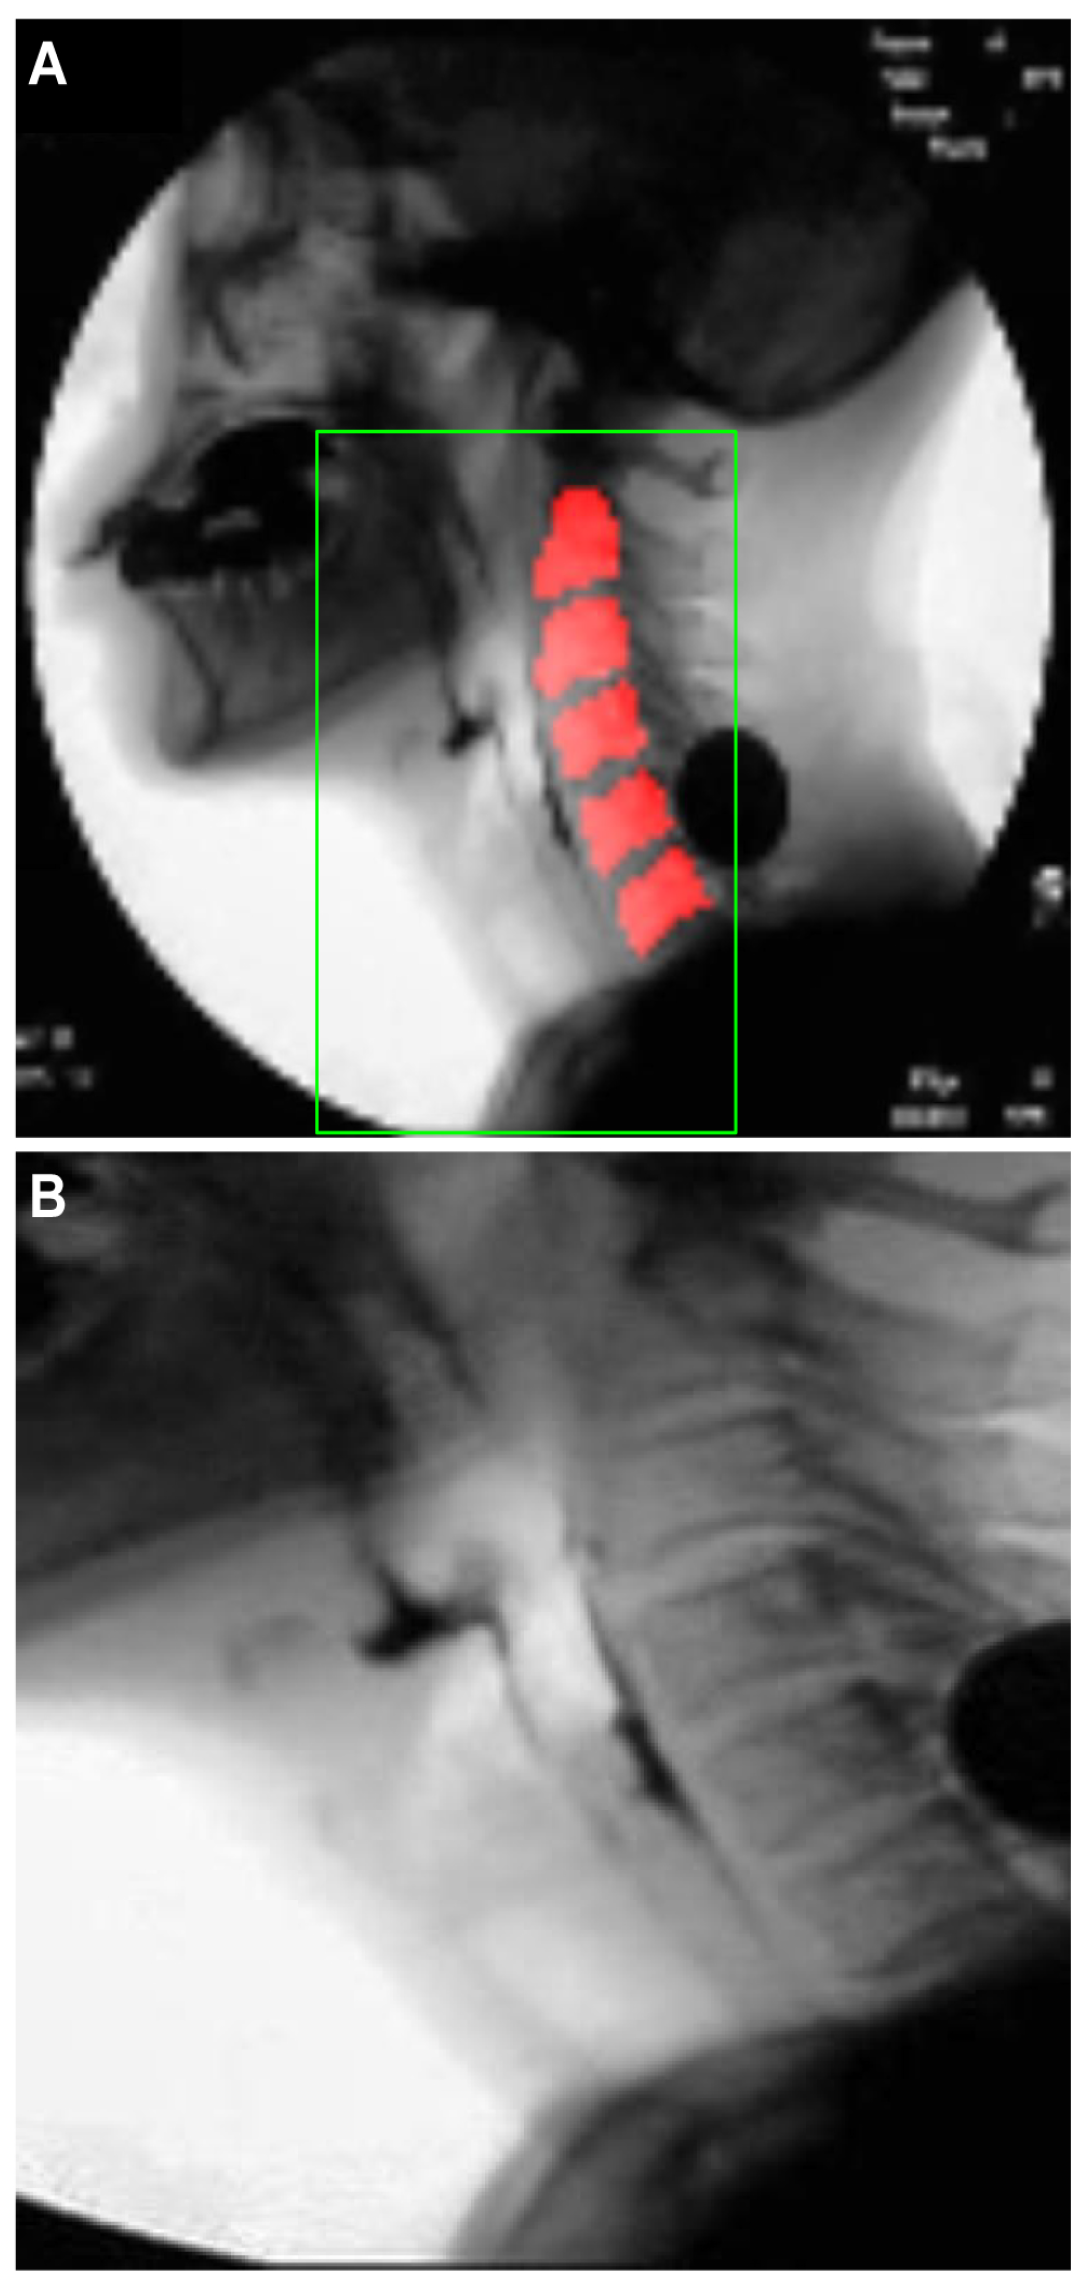

- Deep neural network for the detection of airway invasion:As described in Section 2.3.1, the ROI image (Figure 2C) specified using U-Net is used as the input image for airway invasion detection. To identify the occurrence of airway invasion in individual image frames, we designed a DCNN (deep convolutional neural network)-based classifier. Based on the position and shape of the bolus in the image, the classifier distinguishes whether the bolus is passing normally through the esophagus (normal swallowing action) or whether airway invasion has occurred.A deep neural network contains numerous connections between neurons, and a weight is assigned to each connection. The deeper the network is, the greater the number of weights to be learned, where this increase scales exponentially; consequently, sufficient data are needed to prevent overfitting. Therefore, among the models that can be effectively trained on limited data, in this paper, we choose a CNN based on an Xception module [27]. The Xception architecture not only reduces the number of parameters to be learned by performing convolution on each channel of the image, but also has the advantage of efficiently utilizing spatial and cross-channel correlations in the image (Figure 4). Additionally, by means of residual connections, the degradation problems that can occur as the network deepens can be avoided. In the Xception architecture, data are processed through three flows, namely (1) the entry flow, (2) the middle flow, and (3) the exit flow, and this architecture consists of convolutional layers with a total of 36 3 × 3 filters. All common convolutional and separable convolutional layers are followed by batch normalization [28].For airway invasion detection, we defined the image frames corresponding to instances of airway invasion as the positive class (Figure 5A) and the remaining image frames as the negative class (Figure 5B) and designed a CNN classifier using the Xception architecture with a binary output. Among the 15,335 positive image frames and 252,413 negative image frames included among all 319 video files, seventy percent of the videos in each class were used as training data, and ten percent were used for the validation of the trained network. The remaining 20% of the videos were used as test data to evaluate the final performance of the proposed classifier. Table 1 shows the total number of image frames used in the experiment and the numbers of frames in each class used for training, validation, and testing.In this study, we used an Xception module [27] pretrained on ImageNet and fine-tuned through transfer learning [25] on videofluoroscopic image data (Figure 4). The pretrained Xception module takes an image with 3 channels and dimensions of as the input, whereas a video fluoroscopic image is a grayscale image with a single channel. Therefore, we used the same grayscale ROI image resized to as the input to each of the three channels. The transfer learning procedure increased the validation accuracy by approximately 5% compared to training from scratch.